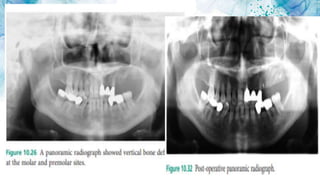

2.8 Classification of Alveolar Ridge

Defects